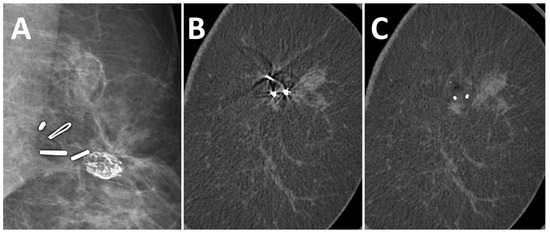

3.2. Effect of MAR on Artifacts

3.3. Effect of MAR on Image Noise and Image Quality

3.4. Detectability of Breast Lesions